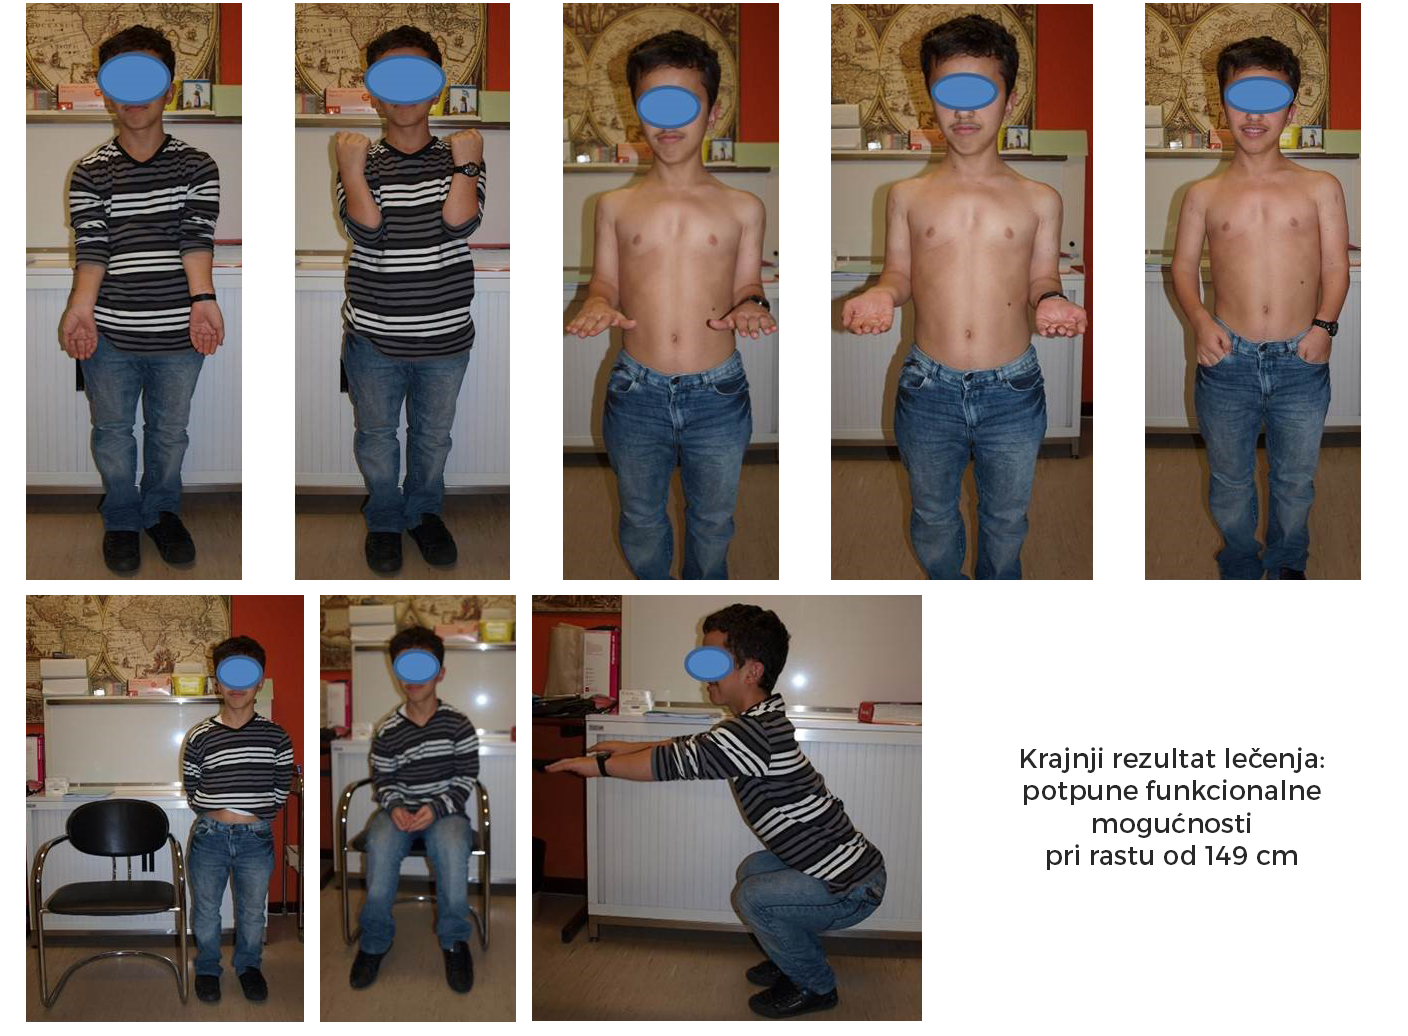

Slede primeri takve rekonstrukcije ekstremiteta (iz arhive prof. D. Popkova i Atlas klinike).

*Među etapni rezultat: Produženi donji ekstremiteti, ali predstoji još produžavanje nadlaktica.

*Etapa produžavanje nadlaktice.

*Još jedan primer pacijenta sa pseudoahondroplazijom.